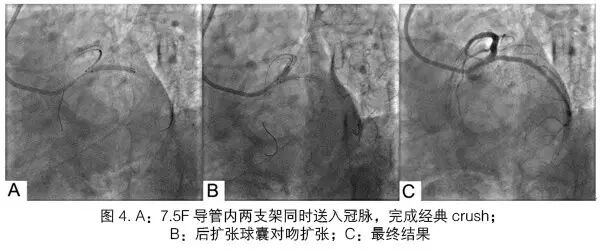

北京友谊医院心血管中心在国内较早使用6.5F和7.5FSheathless Eaucath导引导管,完成的病例多为冠状动脉复杂病变[7],包括CTO、分叉、迂曲钙化病变等,无一例输送失败,也无桡动脉严重并发症出现。而且,我们发现使用4F鞘管完成造影后通常也可以使用7.5F Sheathless Eaucath导引导管。但不建议使用6F鞘管,可能会出现穿刺部位渗血(因为7.5F Sheathless Eaucath导引导管外径小于6F鞘管)。在处理CTO、迂曲钙化等病变时,由于该导管管壁较厚,支撑力很强,在许多病例中,即使使用JL和JR等GC也可获得较强的支撑力,能完成PCI术,更强支撑力的GC有PB、SPB、AL、SC等。7.5F Sheathless Eaucath导引导管的另一优势是在分叉病变的PCI中,等同于普通GC 7F的管腔,而且其内腔非常光滑,输送器械非常方便。7.5F导管能完成大多数的分叉病变技术,例如:直径分别为3.5 mm和3.0 mm的支架可以直接完成经典Crush技术(图4),无需球囊过渡(Step Crush技术);直径4.0 mm的球囊和3.0 mm的支架也可以在腔内完成Reverse Crush技术。部分患者还使用了三个球囊同时对吻扩张(图5)。使用7.5F无鞘导管处理分叉病变,缩短了操作时间,降低了操作难度,也减少了患者的痛苦。